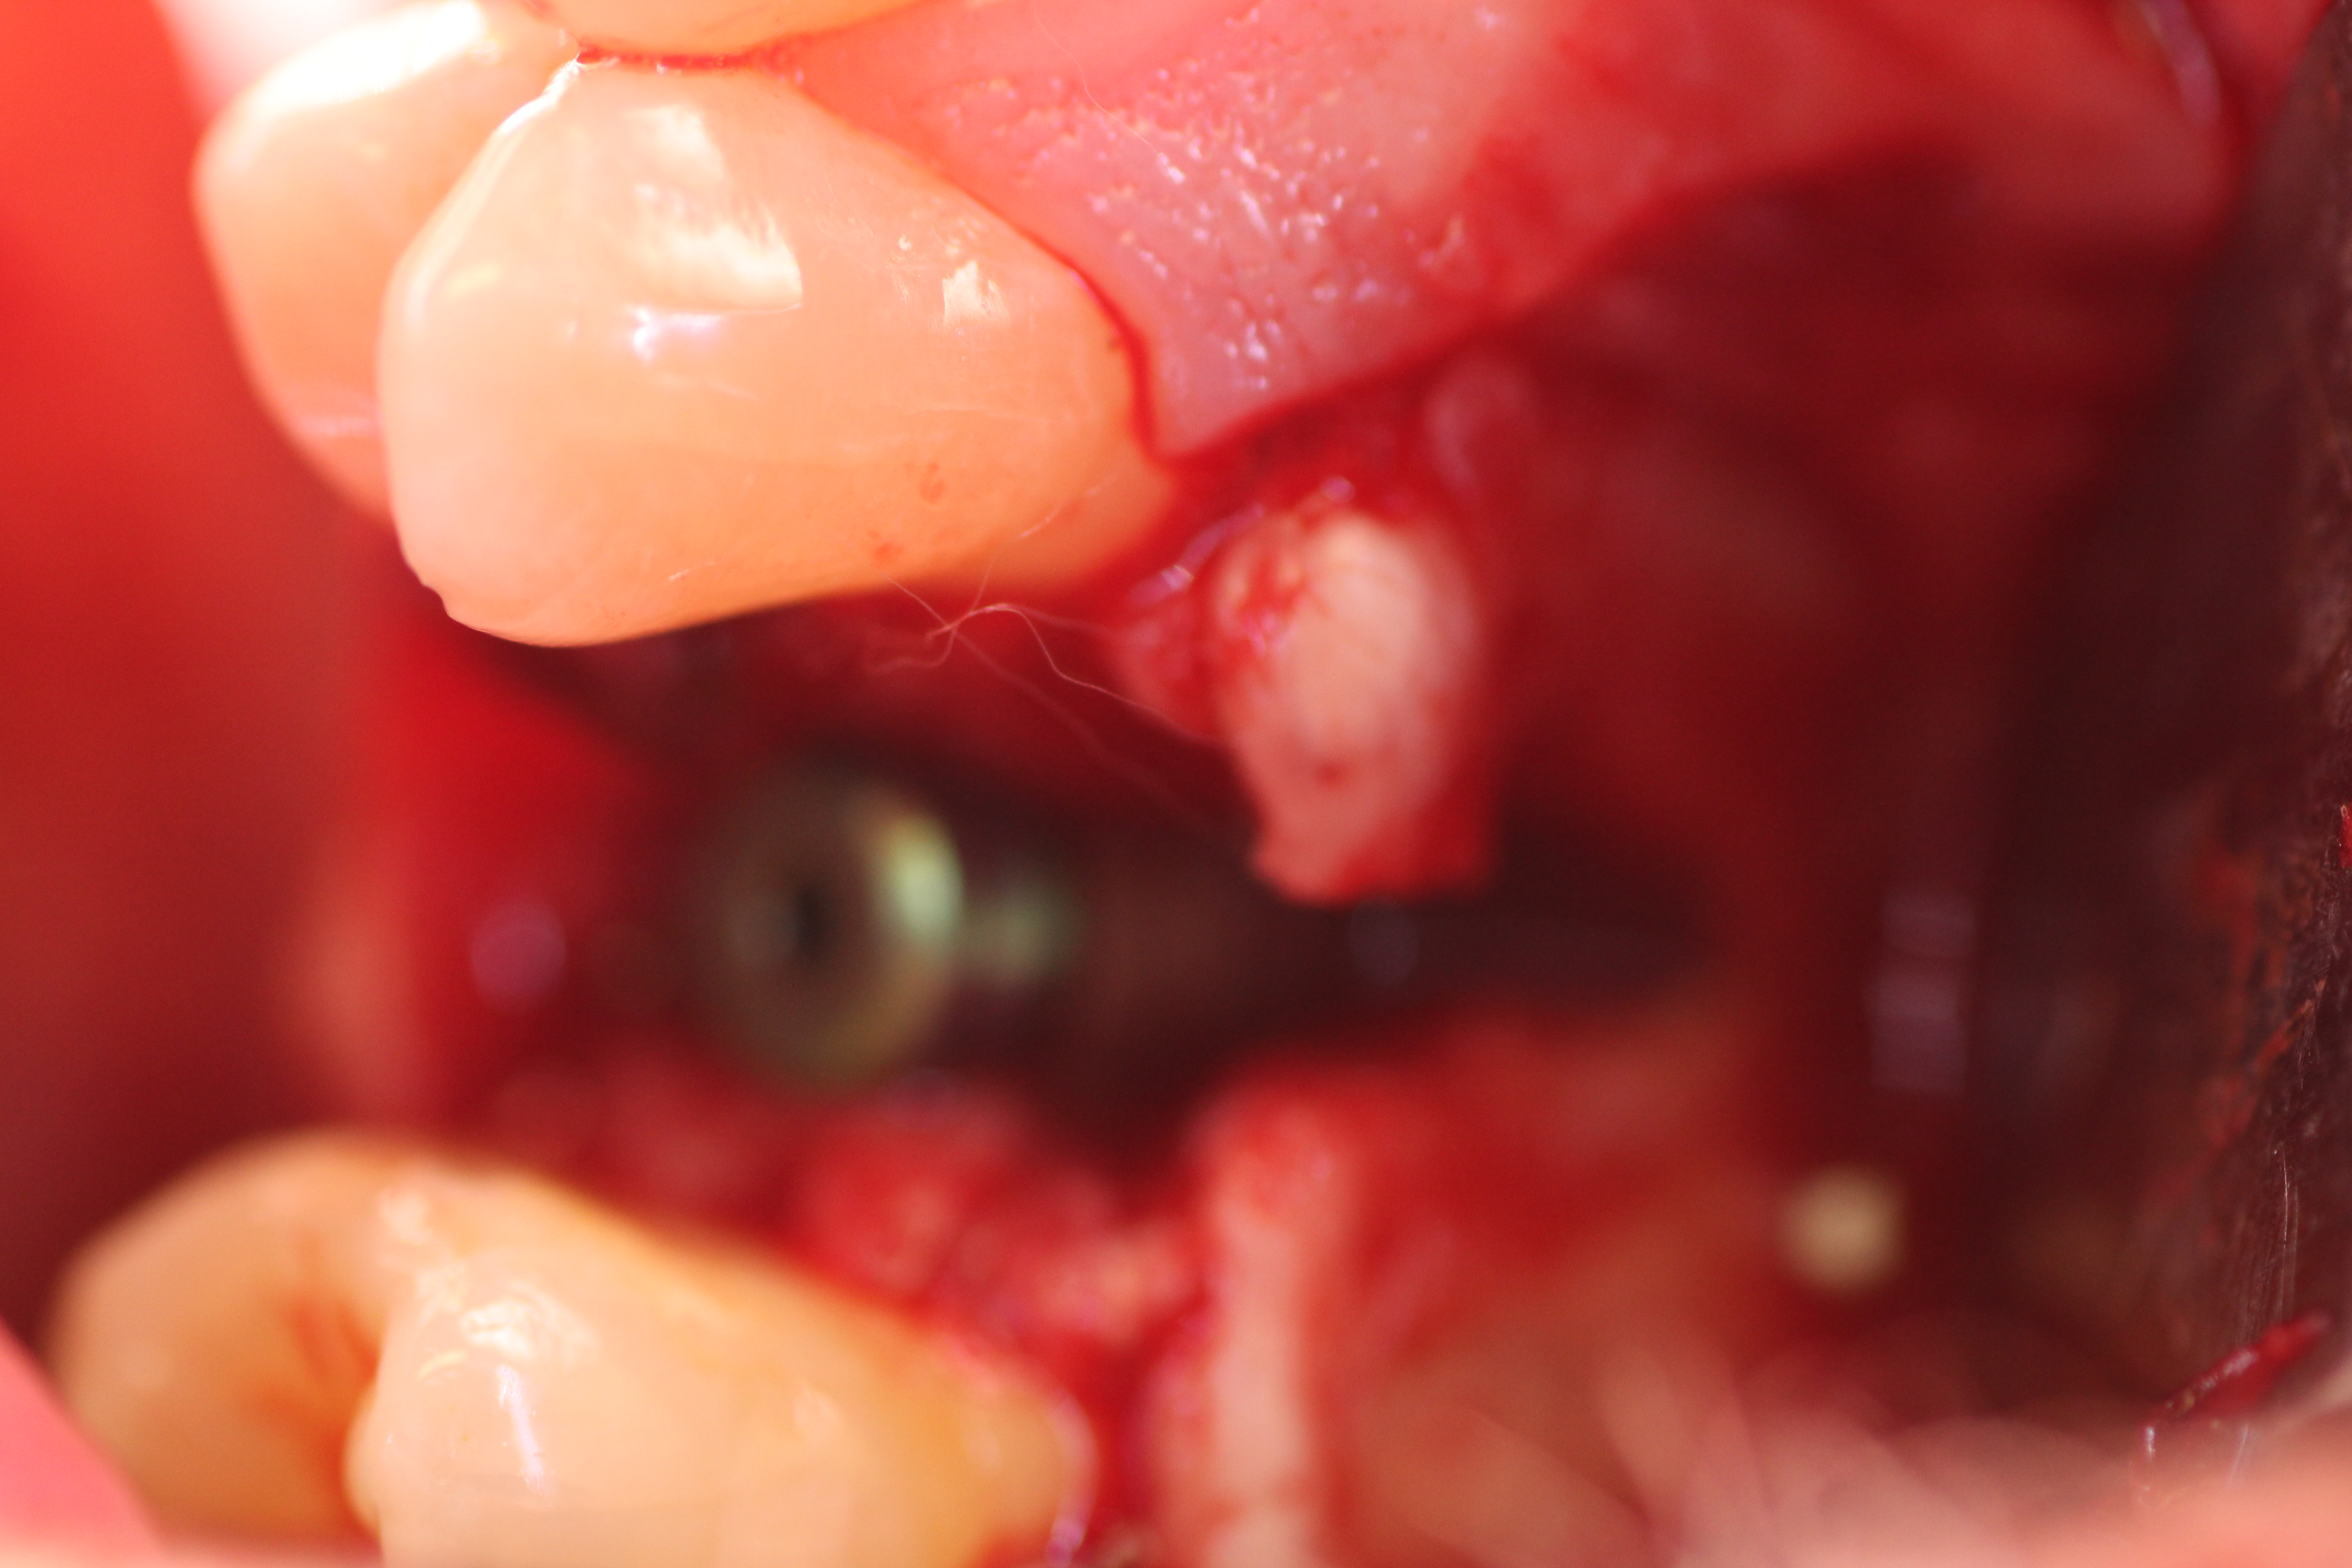

- Implant is in place.

- Bony defect measuring 3mm x 10 mm.

- Human cadaver particulated bonegraft packed into the defect followed by coverage with collagen membrane.

- Area is closed up with PTFE sutures.